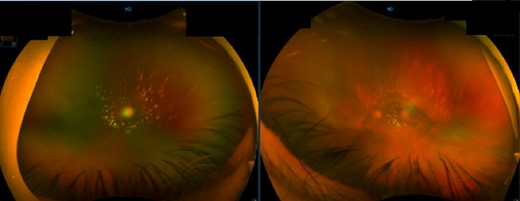

This case involves a 74-year-old male with a medical history of atrial fibrillation and a liver transplant for alcohol-associated cirrhosis, who presented with progressive vision impairment characterized by bilateral floaters, flashes and photophobia severely affecting his professional abilities as a neuroradiologist. This impairment was attributed to bilateral posterior vitreous detachment (PVD) with opacification (Fig. 1). The complexity of his case was heightened by his post-transplant immunosuppressive regimen, consisting of mycophenolate and tacrolimus.

Fundal image of right and left eye. Right eye: large PVD with opacification and some vitreous cells. Left eye: nuclear sclerosis of intraocular lens and large PVD with opacification.

The diagnostic suspicion was raised with the initial ophthalmological evaluation due to progressive vision impairment (Fig. 1). The subsequent PPV allowed for the collection of vitreous samples, which confirmed the diagnosis of DLBCL through flow cytometry and comprehensive cytogenetic analyses. This highlights the pivotal role of surgical techniques and sampling methods in achieving accurate diagnoses in ocular lymphomas.